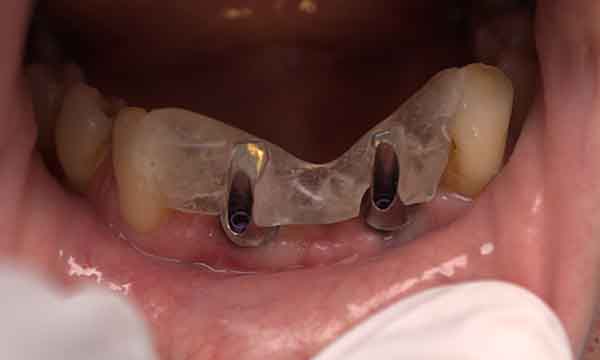

A case of a patient who was a long term resin retained bridge wearer. The resin retained bridge was placed after the patient lost his UL1 many years ago. There was a history of the resin retained bridge lute failing, and due to the loss of the UL1 there was a labio - palatal bone deficit.

A clear acrylic position guide was used to guide implant placement within the aesthetic envelope and guided bone regeneration was used labially to elevate the long standing concavity. A Bonded crown was used to restore the implant and at the 12 month follow up, the bone level around the implant remains unchanged and the patient is confidently smiling.

Case C

During Treatment